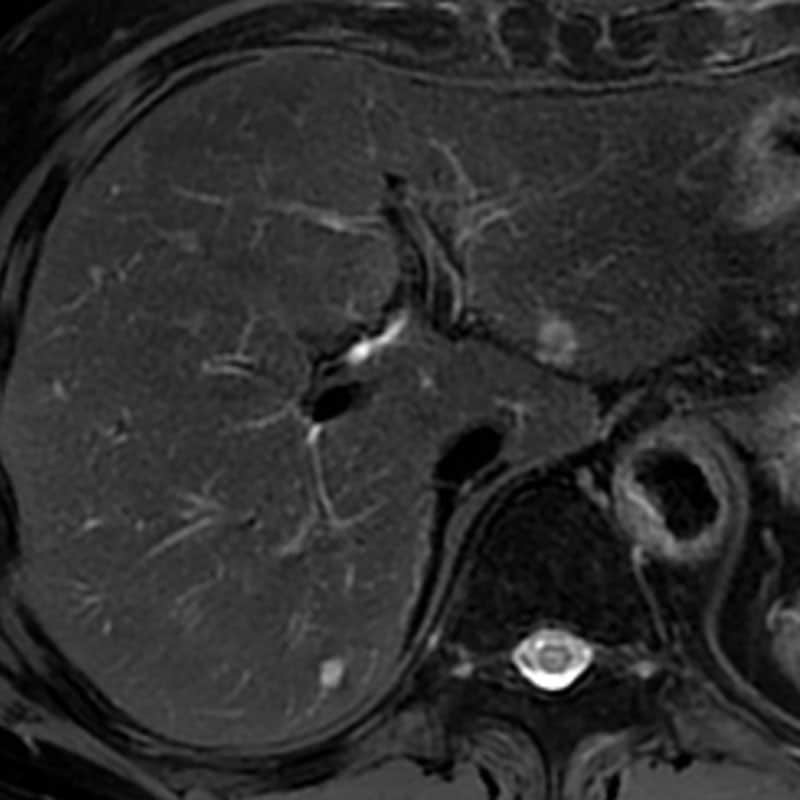

図3.造影T1WI後期相

肝S2結節は早期から後期相にかけて増強効果は乏しい。